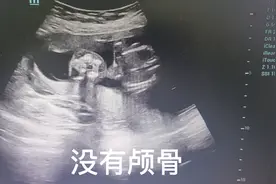

小梅今年28岁,这个孩子是她的第一胎,他们家非常重视这个宝宝。怀孕伊始,小梅就向公司请了产假。 小梅早上和晚上回去公园散步,白天就在家里做做瑜伽或是看书。小梅怀孕5个月的时候去做产检,医生说羊水较多胎位不清,胎心音遥远,很可能是个无脑儿。